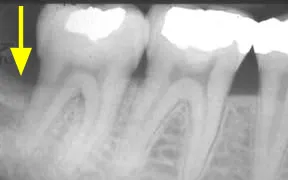

The yellow arrow above is pointing to an area where this patient has suffered some bone loss. The dark area indicates that the bone is not as dense and without treatment the prognosis for this tooth would be poor.

A bone graft procedure was performed and the yellow arrow above is pointing to the regenerated bone. This area is much denser with bone than the same area in the image to the left. The prognosis for this tooth is now excellent.